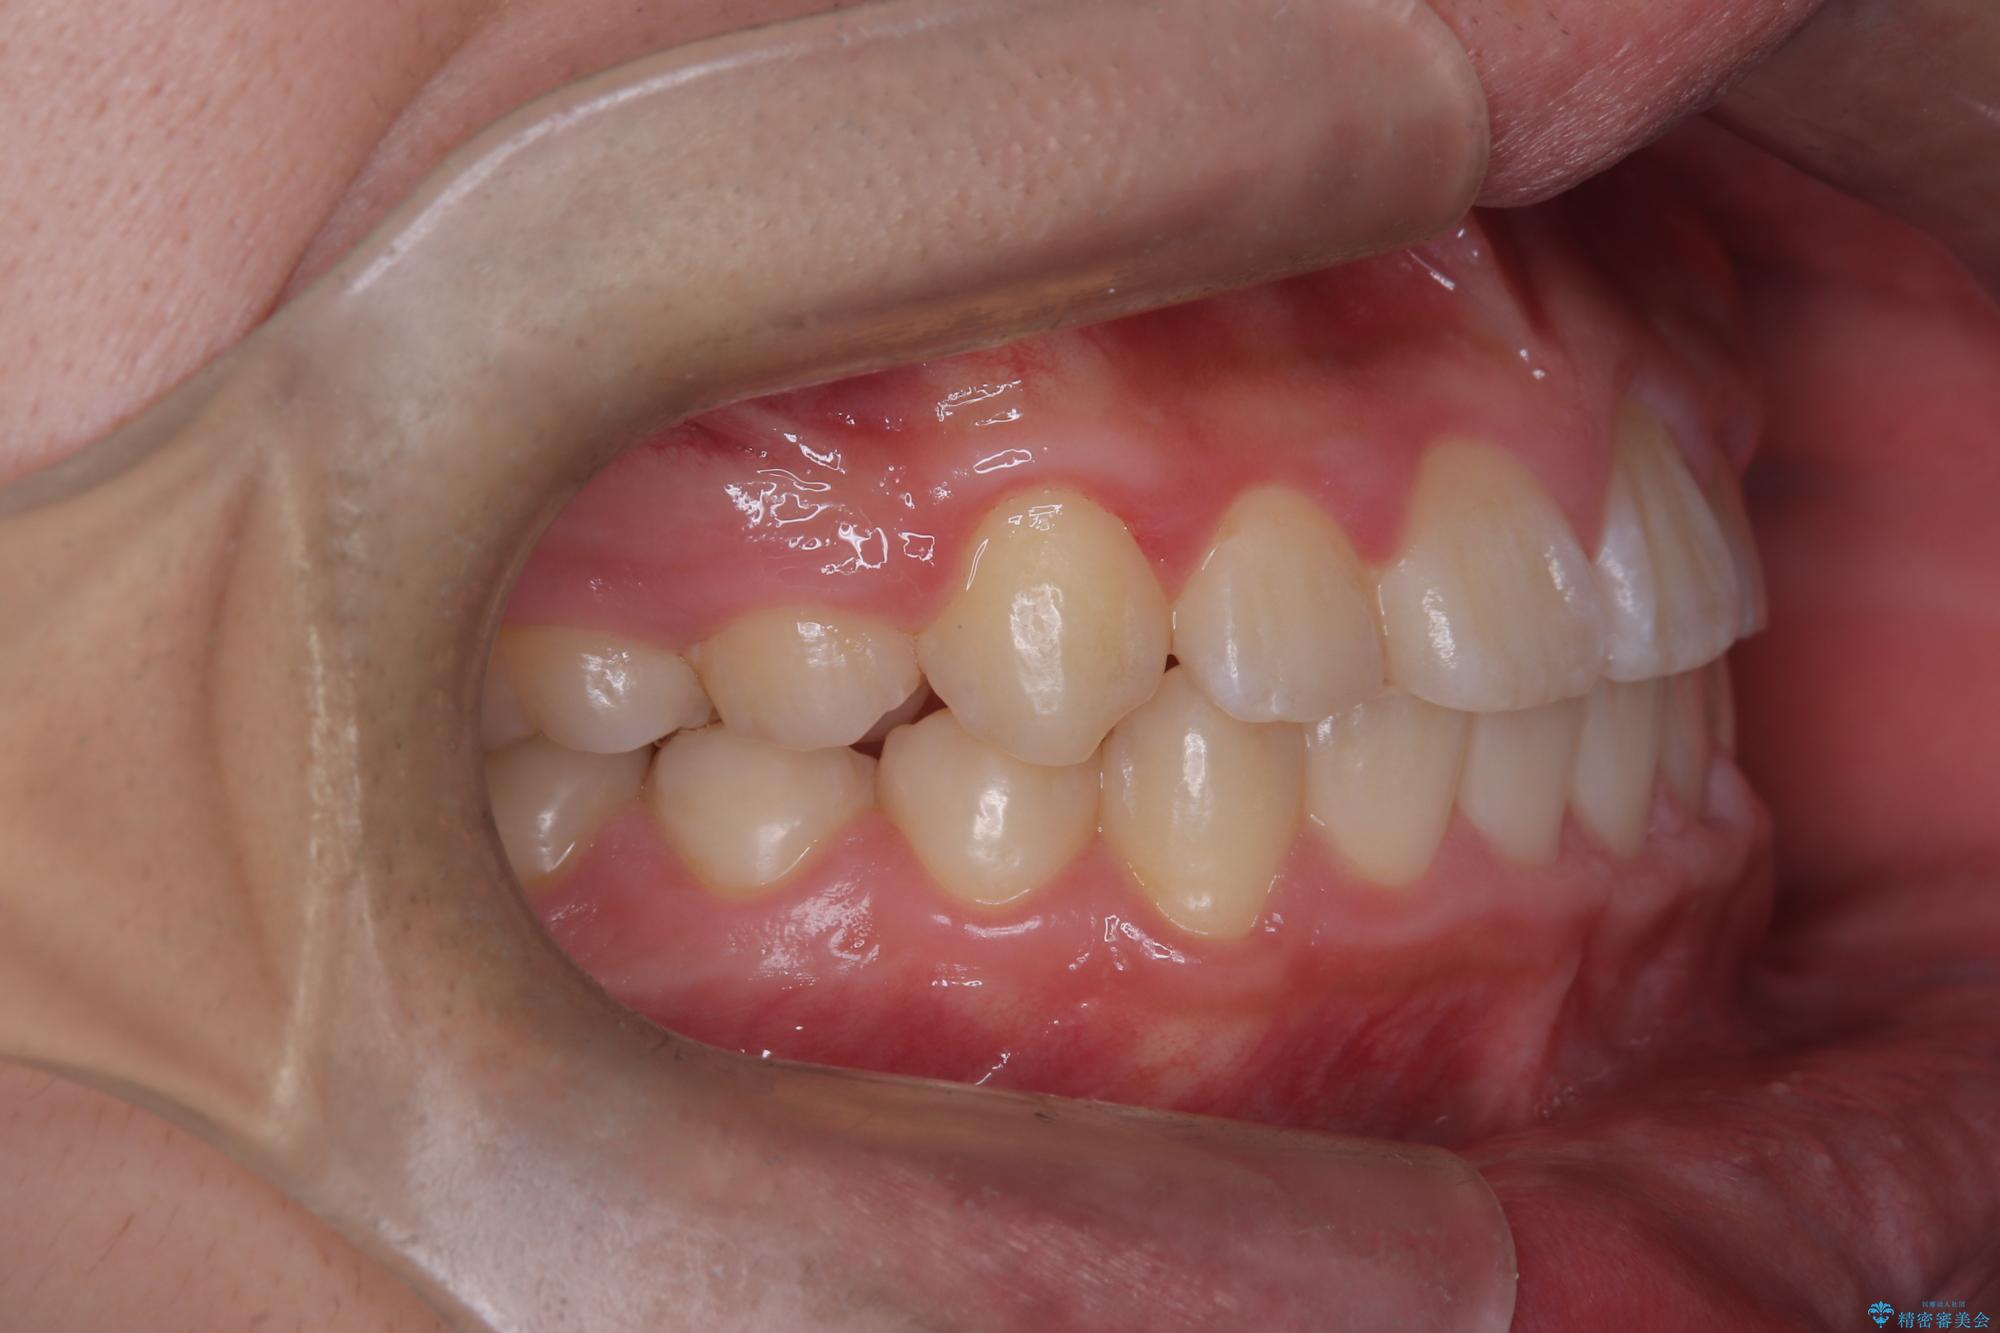

八重歯・歯並びのデコボコとディープバイトを改善した抜歯ワイヤー矯正症例

八重歯などの歯列のデコボコが綺麗に改善され、患者様にも大変喜んでいただけました。また、咬み合わせが深い「ディープバイト」も併せて改善し、見た目だけでなく機能面でもバランスの取れた咬合を獲得しています。